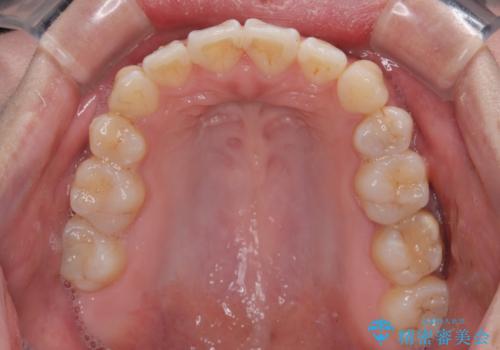

舌突出癖の改善トレーニングは、仕上がり、治療期間、そして治療後の後戻りに大きな影響を及ぼします。

トレーニングをしっかりと行っていただいたため、スッキリとした口元に仕上がりました。